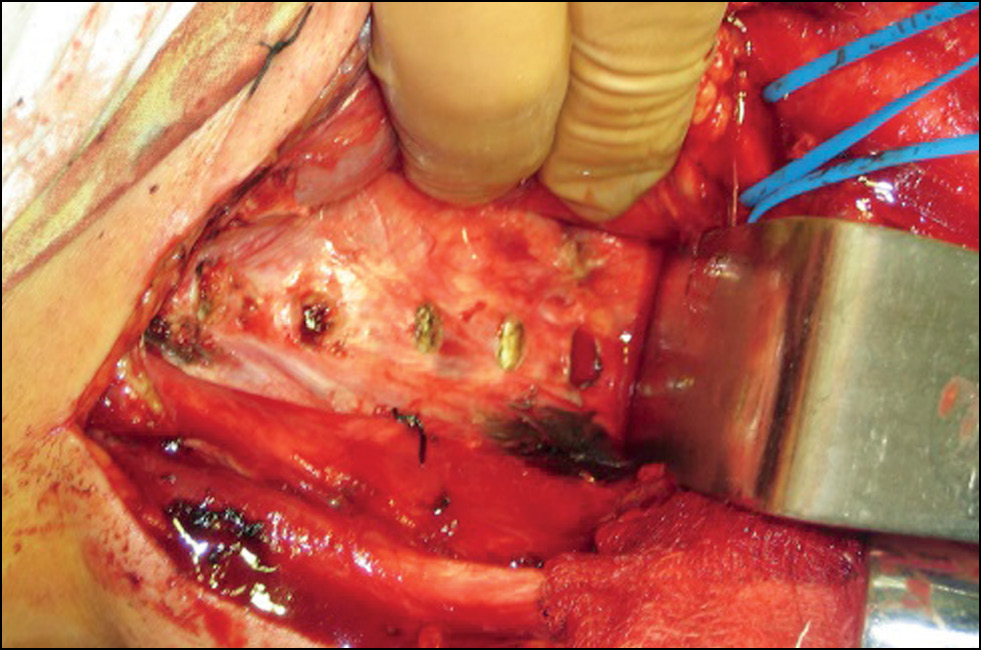

С помощью ручной фрезы, электродрели выполняется корпорэктомия до задней продольной связки и осуществляются спондилодез Th1-Th4 сетчатым имплантатом «Mesh» и фиксация пластиной «Atlantis» (рис. 8).

Рис. 8. Последовательное выполнение корпорэктомии (слева) и спондилодеза сетчатым имплантатом «Mesh» и фиксация пластиной «Atlantis» (справа).

Fig. 8. Sequential corpectomy (left) and spondylodesis with a “Mesh” cage implant and fixation with an “Atlantis” plate (right).

Далее выполняются сопоставление костных краёв раны и костный шов. Дальнейшее закрытие раны стандартно. Если не было контакта с плевральной полостью, то необходимости в дренировании нет (рис. 9).

Рис. 9. Выполнение костной пластики тела и рукоятки грудины.

Fig. 9. Performing bone grafting of the body and manubrium of the sternum.